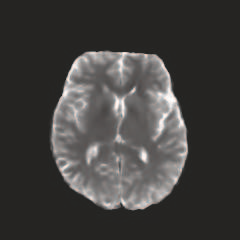

Multi-modal medical image completion has been extensively applied to alleviate the missing modality issue in a wealth of multi-modal diagnostic tasks. However, for most existing synthesis methods, their inferences of missing modalities can collapse into a deterministic mapping from the available ones, ignoring the uncertainties inherent in the cross-modal relationships. Here, we propose the Unified Multi-Modal Conditional Score-based Generative Model (UMM-CSGM) to take advantage of Score-based Generative Model (SGM) in modeling and stochastically sampling a target probability distribution, and further extend SGM to cross-modal conditional synthesis for various missing-modality configurations in a unified framework. Specifically, UMM-CSGM employs a novel multi-in multi-out Conditional Score Network (mm-CSN) to learn a comprehensive set of cross-modal conditional distributions via conditional diffusion and reverse generation in the complete modality space. In this way, the generation process can be accurately conditioned by all available information, and can fit all possible configurations of missing modalities in a single network. Experiments on BraTS19 dataset show that the UMM-CSGM can more reliably synthesize the heterogeneous enhancement and irregular area in tumor-induced lesions for any missing modalities.